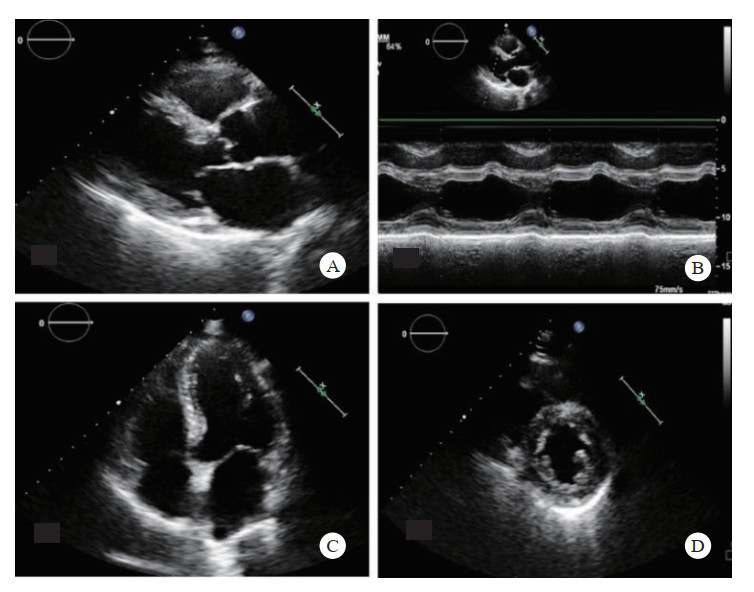

2.4 心脏超声 2.4.1 心脏结构航天员在微重力影响下,体液将发生重新分布,引起容量前后反馈的调控也会发生变化,体液从全身容量血管转移至上身血管,故在返回地面时,回心血量、心腔大小及每搏输出量均可能发生变化[40-41]。研究显示对于模拟失重4周的大鼠,其左心室内径变小,左室容积与每搏量降低[42]。因此应对航天员返回后进行心脏超声检查,了解心腔结构、左室收缩功能及瓣膜、室壁运动情况,评估重力变化对于体液及心功能的影响。

超声快速筛查:目测法观察心腔大小、比例及室壁运动、室壁厚度、心包有无积液,同时快速观察有无血流动力学改变。扫查切面有(图 8):左室长轴切面、心尖四腔心切面、左室M型、左室短轴切面,检查时间不超3 min。

| A: 左室长轴切面;B: 左心室M型;C: 四腔心切面;D: 左室短轴切面 图 8 心脏快速检查切面 |

心包积液为心脏最大舒张期壁层与脏层之间的液性暗区,胸部严重冲击伤时导致心肌出血或心脏破裂,积血在心包内迅速聚积,甚至引起心包压塞。此时航天员可出现呼吸困难、面色苍白、脉搏细弱、血压下降、心音遥远、颈静脉怒张。应立即行心包超声检查,也是休克及急救超声心脏检查的重点部分,方法容易掌握、检查时间短、效果确切。检查切面类似上述心脏快速筛查切面(图 4)。心包积液量的评估见表 1。如确诊大量心包积液后立即可在超声引导下行心包穿刺术,将穿刺针经胸壁刺入心包腔,行减压引流,并确认引流管位置后立即后送。多中心研究证实了超声引导心包穿刺术的安全性[43],纳入研究的各个医疗机构穿刺成功率均较高(91.7%~99%),并发症发生率较低。进针位置多在近心尖部,即锁骨中线外第5~6肋间交界处,检查时间不超2 min。